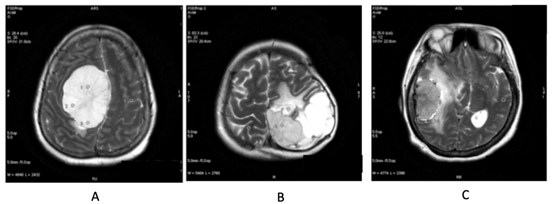

In our study showed that tumor volume as suggested by Hale et al. as the strongest predictor of atypical meningioma, didn’t always correlate with meningioma grade. In our samples there were 6 (37.5%) meningioma WHO grade I with tumor volume more than 50 cm3, with the biggest volume 252.4cm3 (Figure 1) and 1(33%) of atypical meningioma (WHO grade II) with tumor size 28.5 cm3. Hale also suggested that peritumoral edema as predictor of higher grade meningioma. In our study we found 1 case of anaplastic meningioma (WHO grade III) with mild edema and conversely, 44% of meningioma WHO grade I with severe edema (Figure 2). In that study also found that tumor along the falx and convexity were more often atypical than in skull base or posterior fossa. In this study, samples of meningioma WHO grade I mostly (37.5%) located in convexity, 25% in falx and in atypical meningioma WHO grade II turned out 67% located in skull base (Figure 3). That study also found that tumor necrosis was associated with an increased risk for atypical meningioma. In this study, we found 67% of atypical meningioma WHO grade II without tumor necrosis and 44% of typical meningioma WHO grade I with tumor necrosis (Figure 4). 1 case of anaplastic meningioma (WHO grade III) in our study had large tumor volume (>50 cm3), located in convexity and with tumor necrosis although there was one predictor that didn’t suit which in this case had mild peritumoral edema (Figure 5).

Figure 1 Female, 44 y.o with meningioma fibroblastic type, WHO Grade I; tumor volume was 252,4 cm3.

Figure 3 (A) Meningioma at parasagital falx cerebri, fibroblastic type, WHO grade I. (B) Meningioma at left falx cerebri, microcystic type, WHO Grade I. (C) Meningioma at right temporal convexity, turned out to be microcystic type, WHO Grade I.